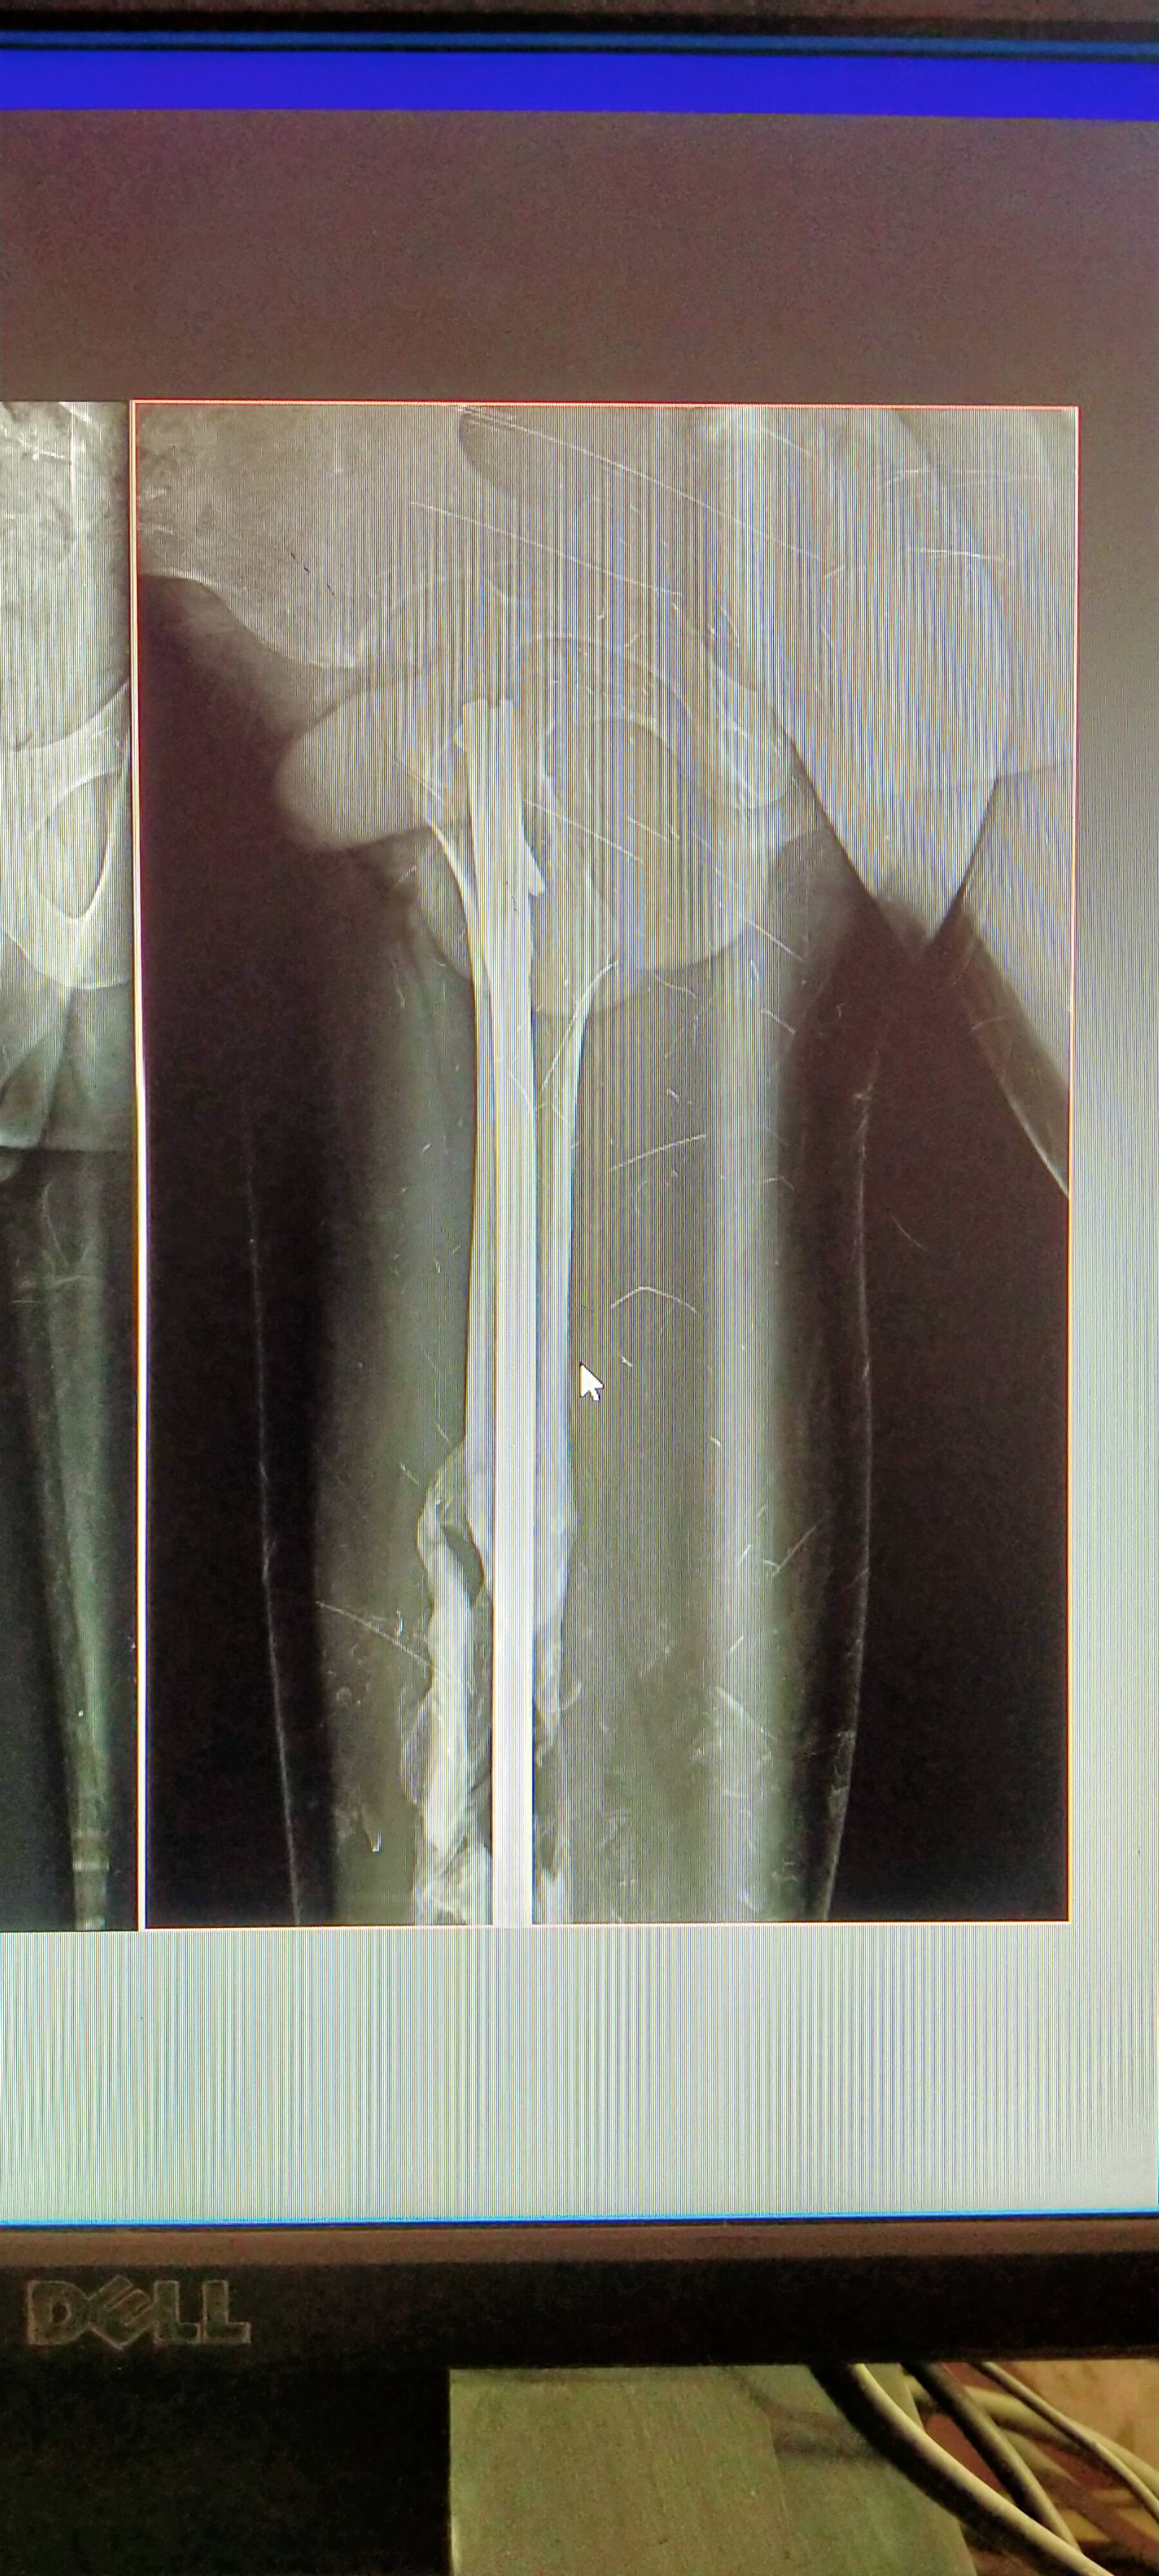

Hello sir my opresan time 3 month , at Apollo hospital guwahati me opresan hua h ,, aap btaiye kitna time lgega. Bone ready hone pr please sir aap btao exary dekh ke